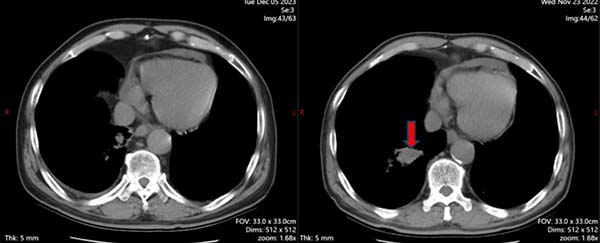

平静的日子持续到2022年冬天,H先生咳嗽喘憋的症状再次加重。这一次,病灶出现在了右肺。凭借职业的敏感性,我意识到这极有可能不是旧敌的重来,而是一个新的“敌人”——第二原发癌。

尽管老人年事已高,且身体历经多次治疗,但我们深知,不能放弃。再次气管镜活检成为了关键。当病理结果回报“鳞状细胞癌”时,我们验证了判断。这不是小细胞癌的复发,而是一个全新的、需要完全不同策略去应对的癌症。

我们首先尝试了化疗,但效果不尽如人意。放疗也未能遏制它的势头。那段时间,是病程中最艰难的阶段,看着病灶在影像上进展,我们能感受到他和家人的沮丧。但我们从未停止寻找新的武器。

免疫治疗的出现,为我们打开了新的曙光。在完成了数个周期化疗后,我们为他介绍了免疫治疗。当我向他解释这种疗法是如何激活他自身的免疫系统去攻击癌细胞时,我看到了他眼中重燃的希望。最新一次的评估显示,病情得到了有效控制!这一刻的欣慰,无以言表。